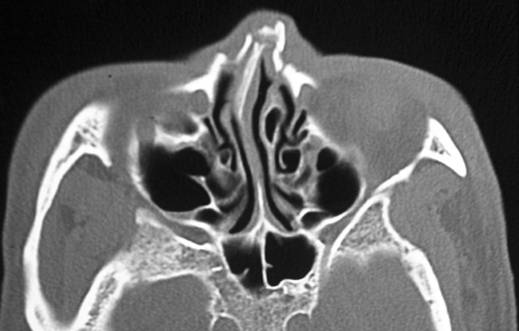

| Battle sign - Think Basilar Skull Fracture | ||||

![]() |

| Normal Tympanic Membranes | ||||

Abnormal tympanic membranes |